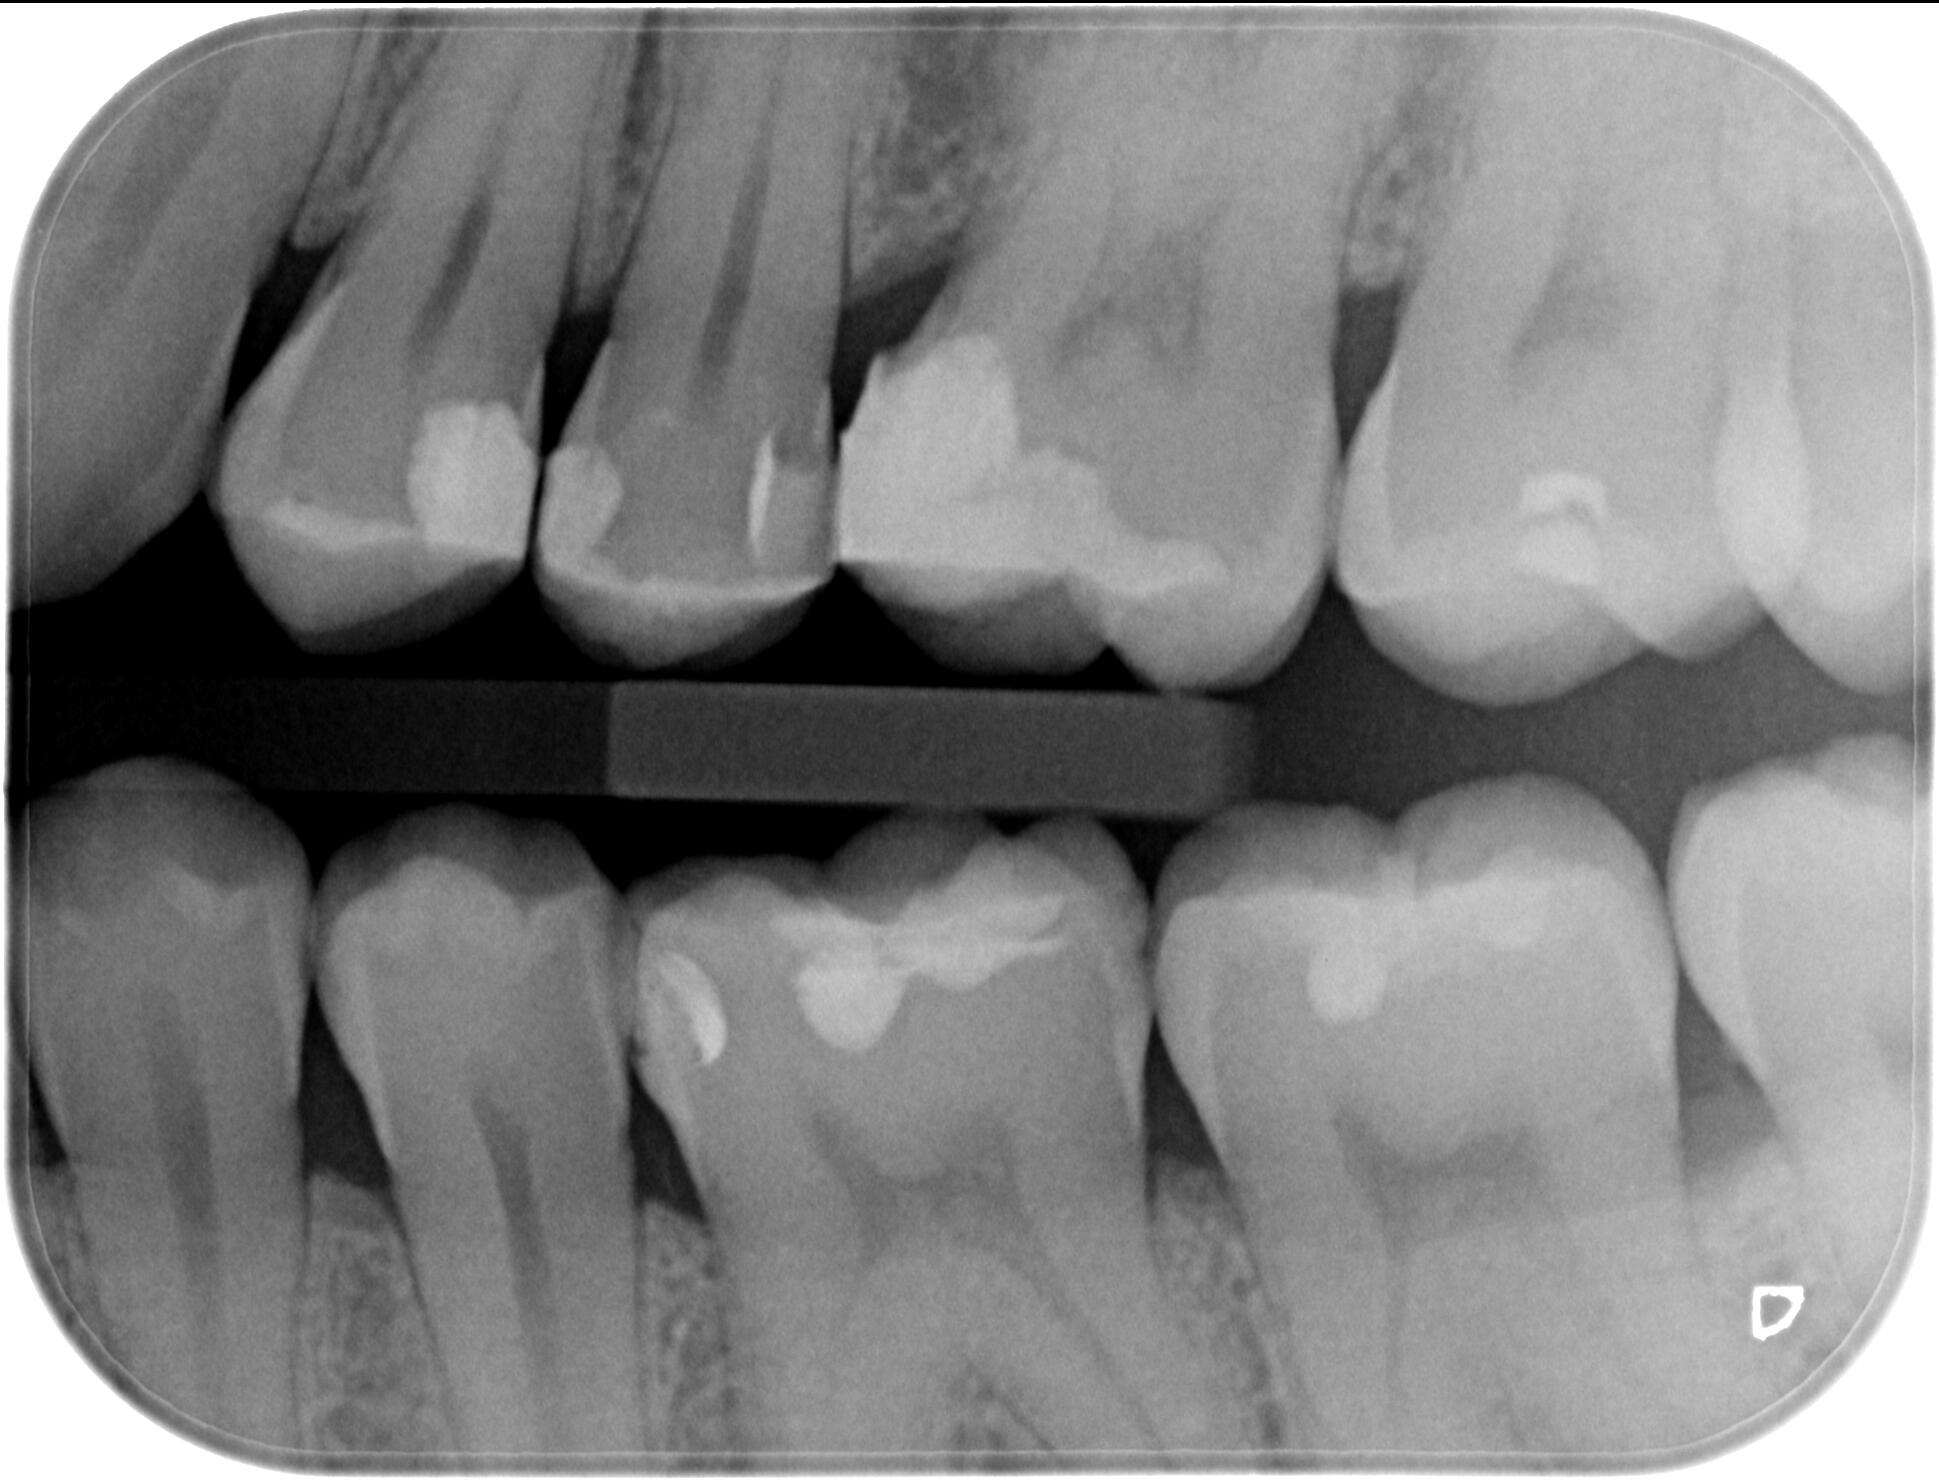

Байтуинг / Bitewing - кариес диагностика

Интраорален рентгенов апарат, характеризиращ се с бързо и лесно позициониране при изследване, за максимален комфорт на пациента.

За още по-голяма безопасност на пациентите, интраоралният ни рентген е оборудван и със специален тубус, който фокусира рентгеновите лъчи само в мястото, което искаме да бъде диагностицирано!